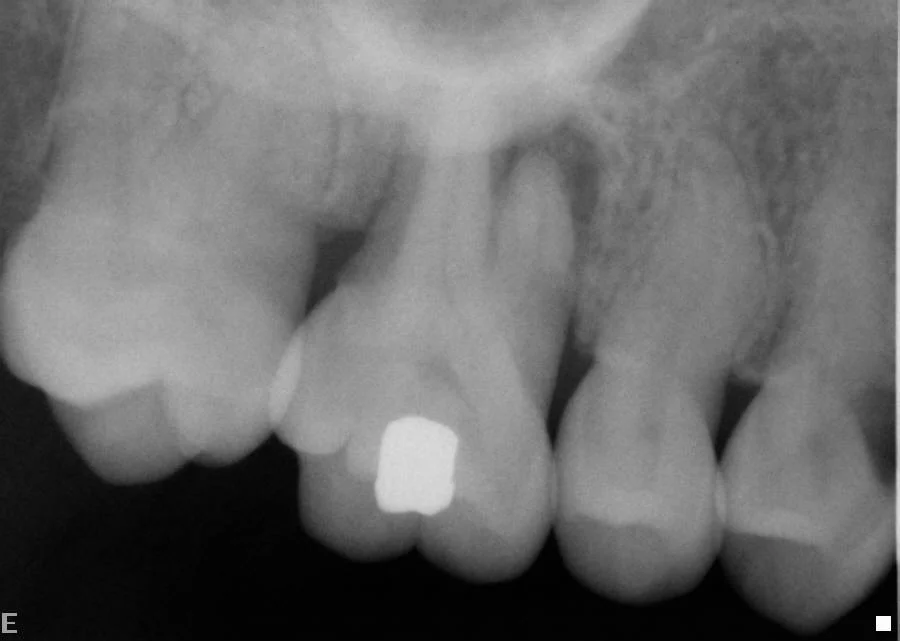

Before: Decay and infection under crown